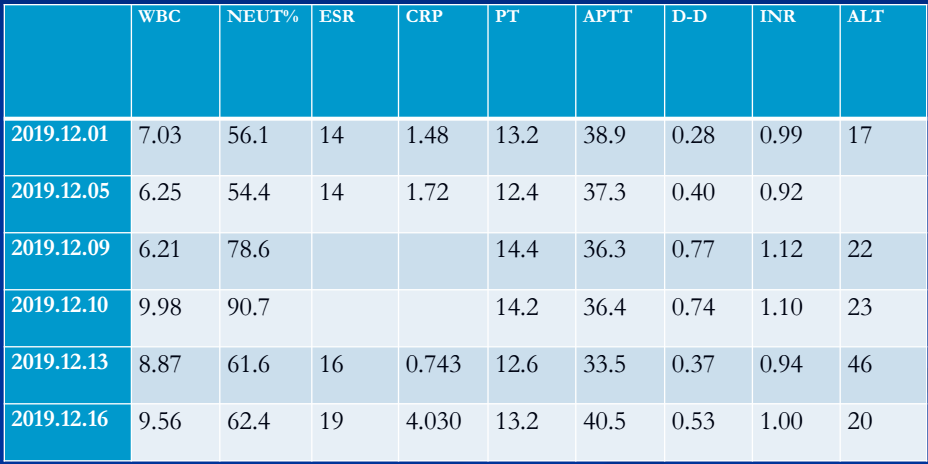

术前术后检验